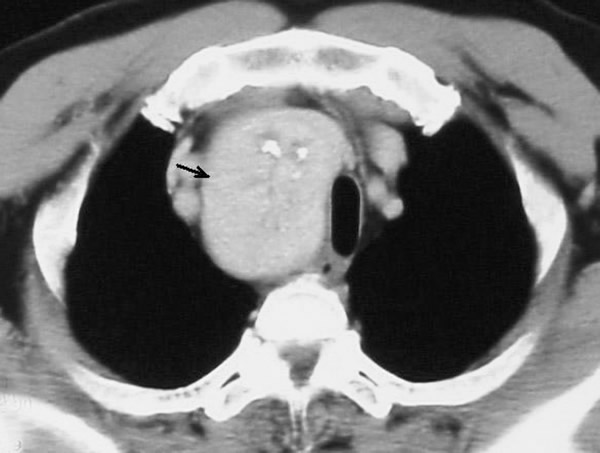

A 58-year-old Chinese man presented with a dry cough of three months’ duration. A chest x-ray at a local hospital revealed "a shadow in the superior mediastinum." A subsequent CT scan suggested "ectopic intrathoracic thyroid" (Figures 1 and 2). His physical examination revealed normal temperature and heart rate, without any signs of hyperthyroidism. Palpation of the neck revealed a non-tender, firm, fixed, and non-pulsatile 2 cm right inferior thyroid mass. A repeat chest x-ray confirmed a mass in the right anteromedial mediastinum, with smooth margins, tracheal compression, and deviation of the trachea to the left (Figure 3). Nuclear Tc99 thyroid scan revealed a cold nodule in the right inferior thyroid gland extending below the sternum (Figure 4). The values of total thyroxin 3 (TT3), total thyroxin 4 (TT4), free thyroxin 3 (FT3), free thyroxin 4 (FT4), and thyroid stimulating hormone (TSH) were all normal. Due to the suspicion of malignancy and to avoid the development of tracheomalacia, surgery was performed to remove the mass.

At operation, through a cervical collar incision 2 cm above the supra-sternal notch, and with the neck extended, the right thyroid gland was explored. The right thyroid gland extended into the middle mediastinum posterior to the innominate vein and lateral to the trachea. The mass was completely encapsulated and hyper-vascular. First, the right middle thyroid vein was ligated and divided, allowing easier access to the intra-thoracic mass. The mass was gently extracted by careful blunt dissection from the mediastinum (Figure 5). The right inferior thyroid vein and artery were exposed, ligated, and divided. Parathyroid glands were not identified. The mass was subsequently removed, preserving the superior portion of the right thyroid gland, and measured 8 x 6 x 5 cm (Figure 6). The recurrent laryngeal nerve was protected during the operation. The wound was closed in layers with a drain in place. The patient was extubated in the operating room and remained stable with no respiratory stridor or airway compromise. The postoperative course was uneventful with no hoarseness, dyspnea, or hypocalcemia (Figure 7). The pathological diagnosis confirmed a benign thyroid adenoma.